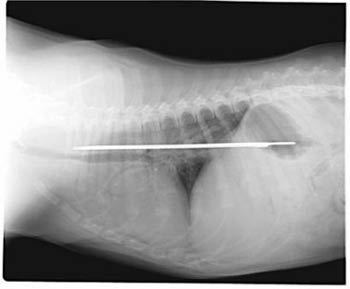

Puppy swallows 13-inch knife, survives

PLANTATION, Fla. - Jane Scarola's veterinarian thought the X-ray was a joke. He's seen strange items get into the stomachs of dogs before, things like kebab skewers and small utensils. But a 13-inch serrated knife that somehow was swallowed by a 6-month-old puppy?

This photo of an X-Ray provided by Imperial Point Animal Hospital in Fort Lauderdale, Fla., Saturday, Sept. 24, 2005, shows a 13-inch serrated knife that somehow was swallowed by 'Elsie' a 6-month-old Saint Bernard puppy. [AP]

Elsie, a Saint Bernard puppy, apparently had the blade between her esophagus and stomach for about four days before it was removed earlier this week in a 2-hour operation.

The puppy has an 8-inch scar, but is fine and back with her family. And the knife is back in Scarola's kitchen, albeit this time wrapped in a towel and placed in a cabinet atop the refrigerator.